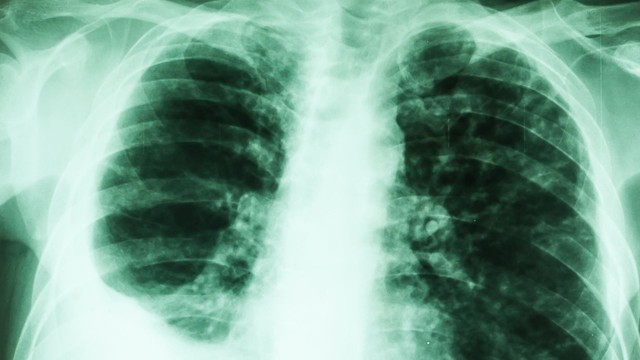

phổi